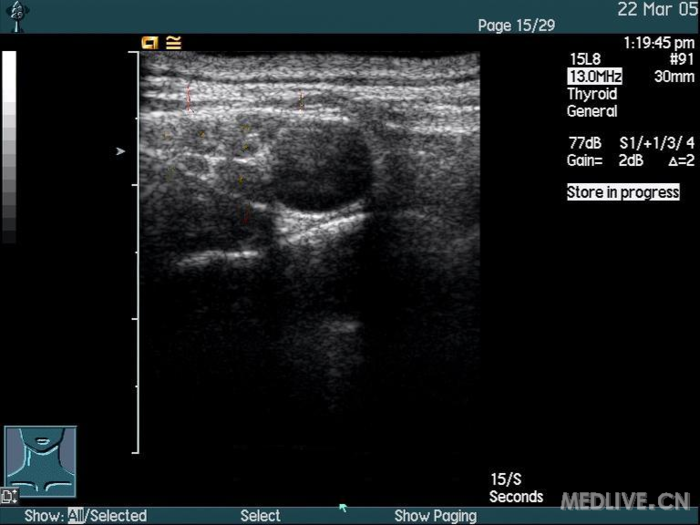

三、超声图像特点:

锁骨上臂丛神经,臂丛神经横断面呈低回声,黑色,周围是三角形的高回声的神经鞘(白色),内侧是圆型搏动环低回声锁骨下动脉,锁骨下动脉位于高回声的第一肋上方。神经鞘内的神经分支形成5-6个黑色圆环,周围被高回声环(纤维膈)包裹分隔成独立的室(这就是锁骨上臂丛神经阻滞单点注药起效慢和阻滞不全的原因)。斜角肌肌肉呈低回声(黑色),下方也可见到呈高回声(白色)的胸膜顶神经分支情况。